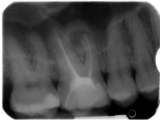

„Videoübertragung der Behandlungssitzung mit Abschluss der Therapie: Die laterale kalte Verdichtungstechnik zur Wurzelfüllung“

Damals zwar bereits ein etabliertes Verfahren, jedoch mit einigen technischen Schwierigkeiten behaftet. So wurden während der Demonstration mehrere Methoden der Entfernung von Guttapercha aus den Wurzelkanälen gezeigt, die von der Handinstrumentation über die 360°-rotierende maschinelle Präparation bis hin zum thermoplastischen Erweichen von Guttapercha reichten. In der zweiten Live-Demonstration wurde dann beim gleichen Behandlungsfall vier Wochen später die laterale kalte Verdichtung von Guttapercha als Wurzelfülltechnik demonstriert. In der Bildergalerie zum Beitrag finden sich die dazugehörigen Röntgenaufnahmen.